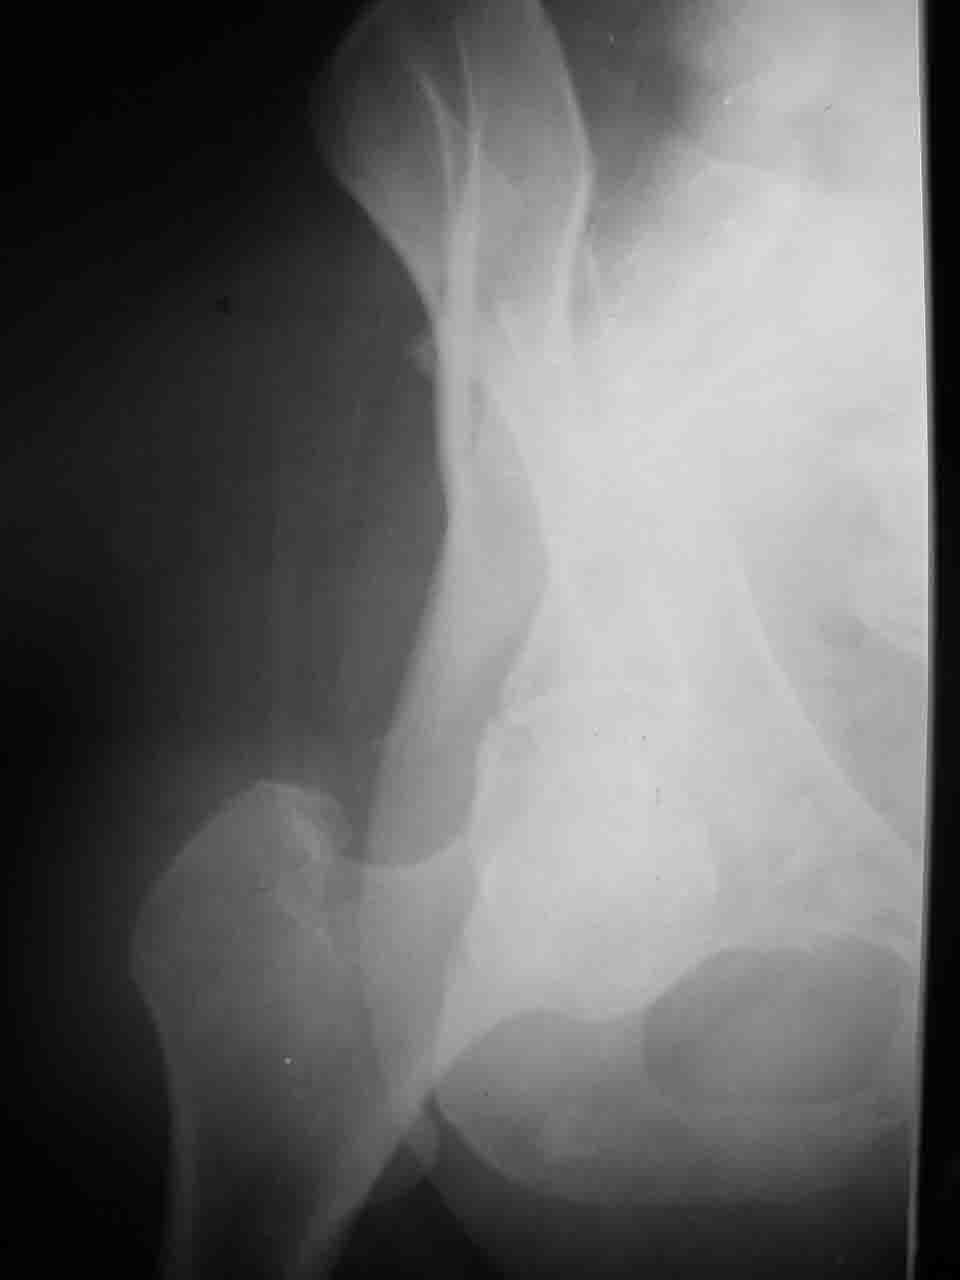

Спасибо за комментарии и рекомендации. Откровенно говоря, больного я прооперировал на прошлой неделе, через 5 дней после аварии и проблем с ним пока никаких нет, на удивление при достаточно обширной диссекции (илиофеморальный доступ) болей практически нет, так что больной самостоятельно садится в кровати, выполняет активные движения в оперированном суставе, сгибая до 60 градусов пока, далее с ассистенцией.

Причиной обращения к сообществу были возникшие непосредственно после операции сомнения и разочарования полученным качеством репозиции: а надо ли было трогать перелом вообще, репозиция передней колонны технически была очень сложна для меня, хотя реконструкции была в той же последовательности, что Д-р А.В.Рунков рекомендовал, в какой-то момент безуспешных манипуляций стал думать о *вторичной конгруэнтности*, которую не так давно обсуждали на

форуме и скелетном вытяжении. С репозицией и фиксацией задней колонны и отдельно задне-верхней стенки впадины проблем не возникло. Послеоп. Рг граммы в приложении. Если возникнут какие-либо дополнения или поправки - был бы признателен.